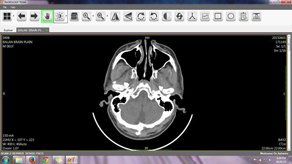

Brand new Workstation for all your radiology needs.

Intelligence lenses on screen to read all images.

World class Kins PACS system with affordable cost.

Art of imaging with proven idea to increase care on patient and revenue.